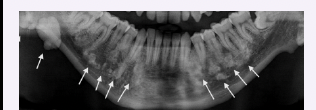

Sickle cell anemia

● Abnormal hemoglobin synthesis resulting in reduced oxygen levels

● Most common in Black Americans

● Moon-shaped red blood cells, swelling of extremities, and episodes of pain during vaso-occlusive crises

● Hair-on-end appearance of the skull, interproximal alveolar bone step ladder patterns

● May experience tonsillitis and adenotonsillar hypertrophy which can lead to airway obstruction and obstructive sleep apnea